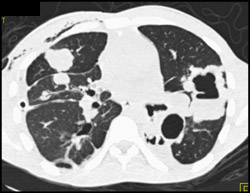

Diagnosis

Normal Arch